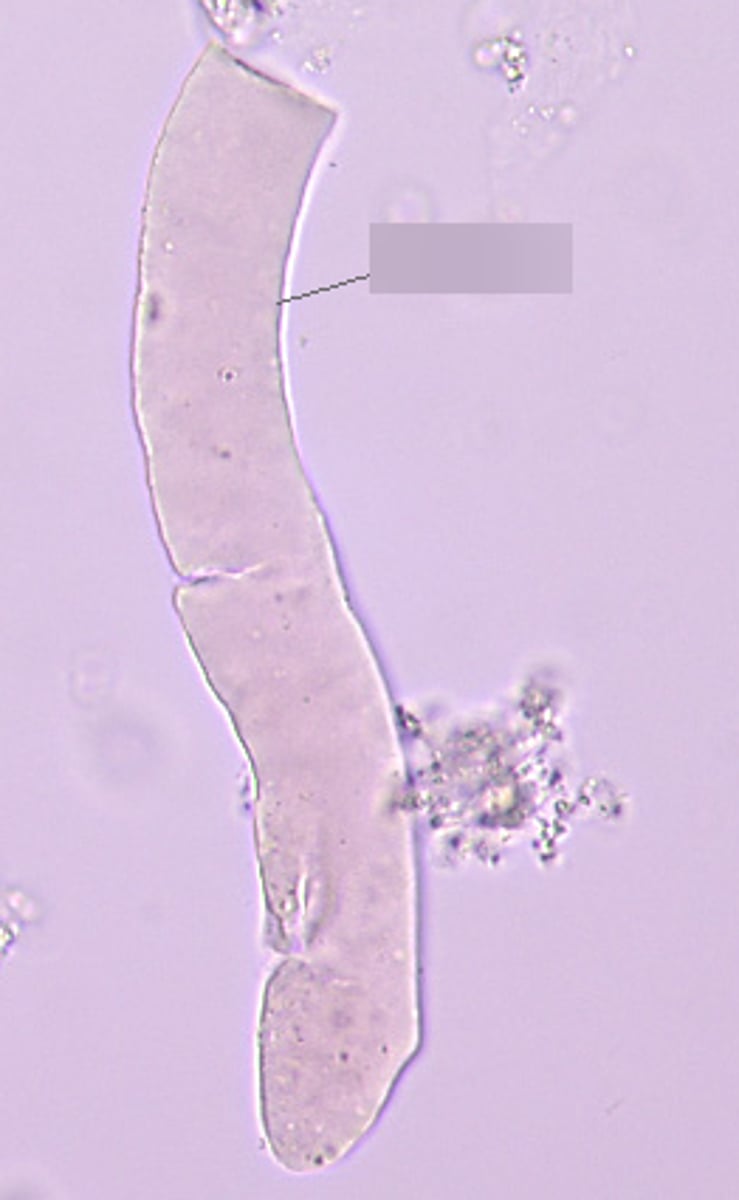

squamous epithelial cell

Folded skirt

Small nucleus, large cell

Lines urethra